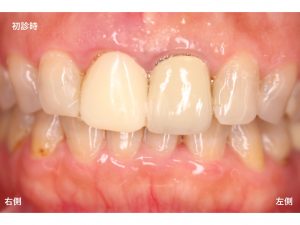

以下が初診時です。

上顎右側の前歯が取れたとのことでした。